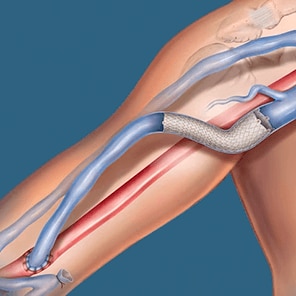

The Covera™ Vascular Covered Stent builds upon proven technologies from the category leader in AV access.

Angioplasty – High Pressure Solutions .035”